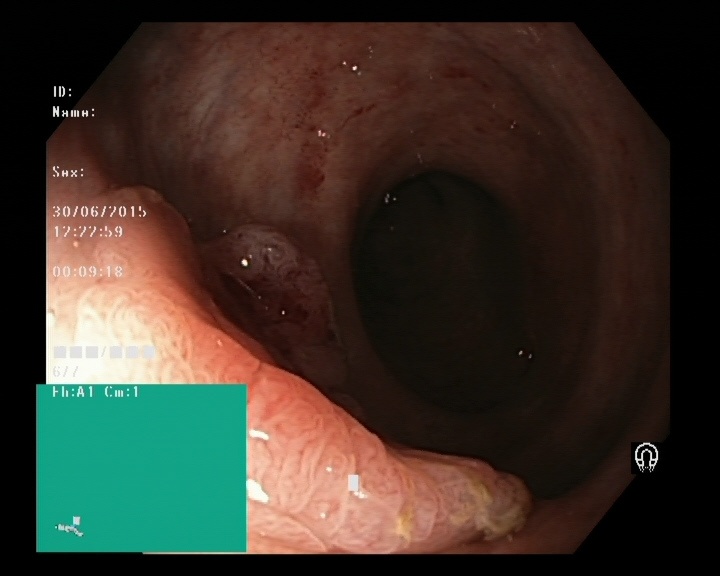

The Kvaris-SEG (Jha et al., 2020c) training dataset can be downloaded from https://datasets.simula.no/kvasir-seg/. It contains 1,000 polyp images and their corresponding ground truth mask as shown in Figure 1. The dataset was collected from real routine clinical examinations at Bærum Hospital in Norway by expert gastroenterologists. The resolution of images varies from to pixels. Some of the images contain a green thumbnail in the lower-left corner of the images showing the scope position marking from the ScopeGuide (Olympus) (see Figure 2). We annotate another separate dataset consisting of 160 new polyp images and use the resulting dataset as the test set to benchmark the participants’ approaches. Figure 2 shows some examples of test images used in the challenge.